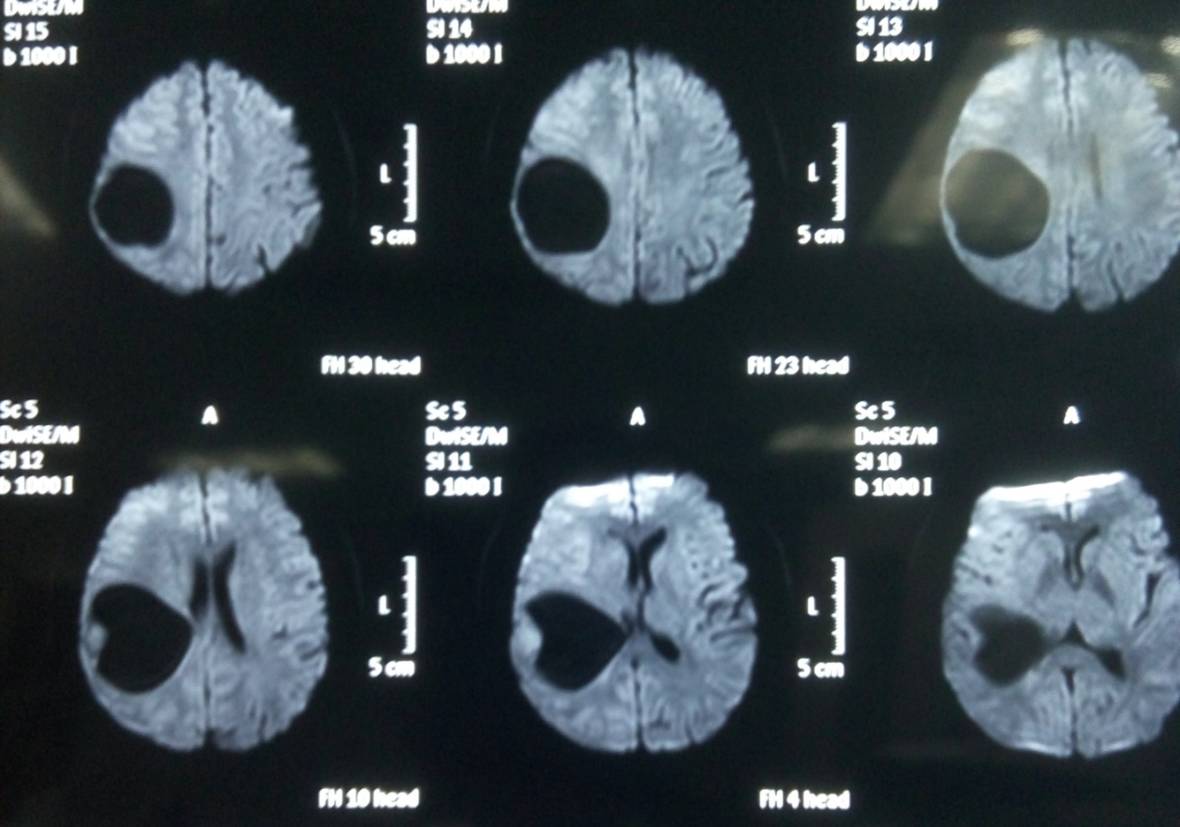

头颅MR示:右颞顶囊性占位伴结节,考虑胶质瘤可能。MRI T1为等信号(图1);T2囊液为高信号(图2);结节为均匀增强(图3);弥散相显示弥散受限(图4)。

图4. 弥散相显示弥散受限。